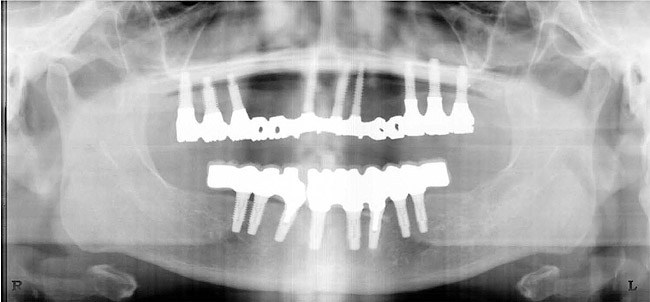

Figure 1  The crown height is measured from the alveolar crest to the occlusal table.

Figure 1

Figure 2  Vertical components of crown height space for a cement-retained restoration.

Figure 2

Figure 3   A crown height space < 15 mm necessitates a PFM material selection.

Figure 3

Figure 4  A crown height space > 15 mm necessitates a hybrid restoration.

Figure 4

Figure 5  The increased amount of metal required for this prosthesis greatly increases the laboratory costs.

Figure 5

Figure 6  The increased amount of metal required for this prosthesis greatly increases the laboratory costs.

Figure 6

Figure 7   A hybrid restoration requires less metal to fabricate.

Figure 7

Figure 8   A hybrid restoration requires less metal to fabricate.

Figure 8

Figure 9  Vertical components of crown height space for a bar-retained implant overdenture.

Figure 9

Figure 10a  Supra-eruption of the opposing arch, thus diminishing crown height space.

Figure 10a

Figure 10b  Supra-eruption of the opposing arch, thus diminishing crown height space.

Figure 10b

Figure 10c  Traditional fixed prosthodontics performed to level the opposing arch and regain sufficient crown height space.

Figure 10c

Figure 10d  Traditional fixed prosthodontics performed to level the opposing arch and regain sufficient crown height space.

Figure 10d

Figure 11a  Insufficient crown height space for bar overdenture because of the vertical dimension of the mandible.

Figure 11a

Figure 11b  Osteoplasty performed at the time of implant placement to gain sufficient crown height space.

Figure 11b

Figure 12  Horizontal spacing needed between the natural tooth and the implants and between the adjacent implants.

Figure 12

Figure 13  Radiograph depicting the necessity of horizontal placement parameters to prevent vertical defects from becoming horizontal defects.

Figure 13

Figure 14  Diagram of potential anterior-posterior spread based on implant placement and arch form.

Figure 14